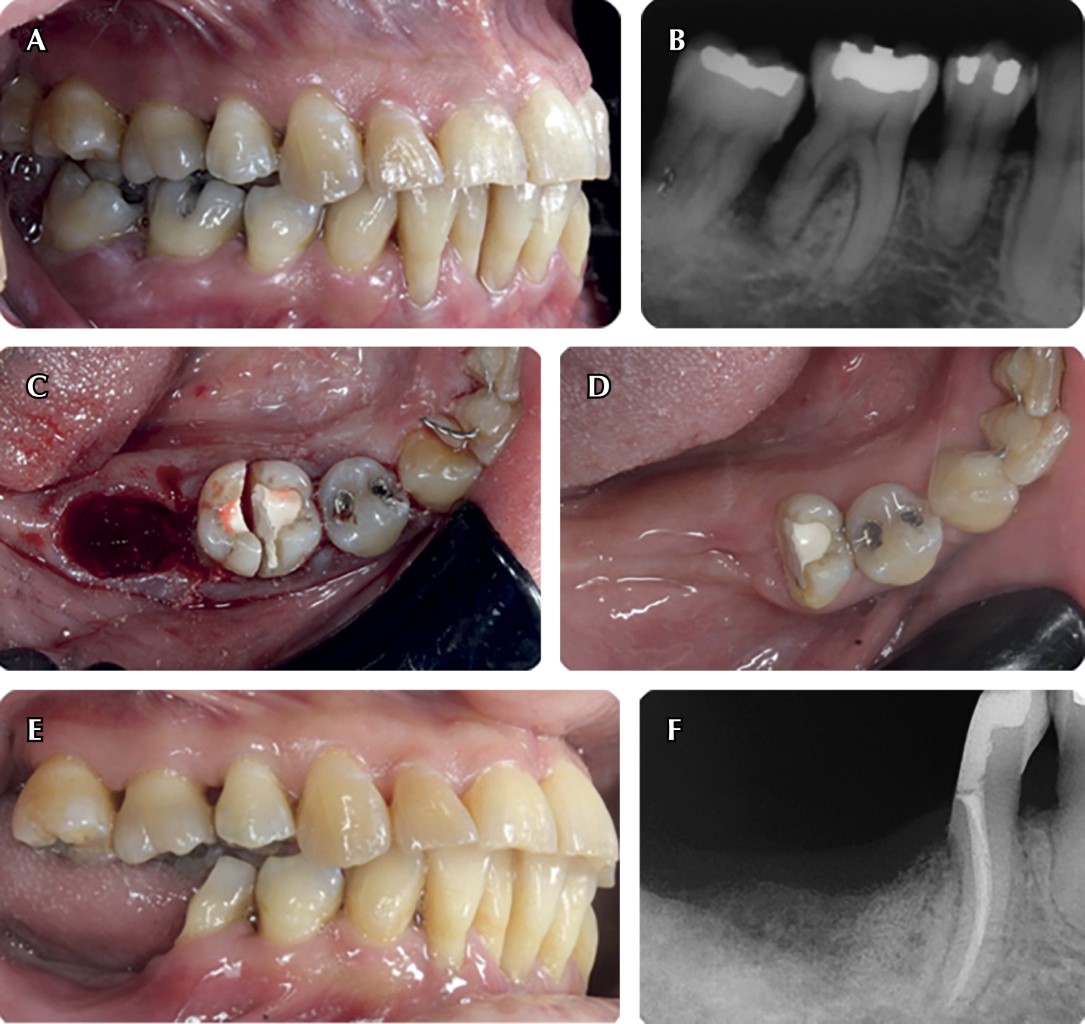

Tunelización

Los molares con furca grado III están en mayor riesgo de extraerse en comparación con aquellas con grado I y II, por lo que son consideradas un desafío desde el punto de vista terapéutico. La tunelización de una furca busca facilitar la higiene por parte del paciente por medio de la creación quirúrgica de un "túnel" accesible para los cepillos interdentales.49

Para que la cirugía sea exitosa es necesario que se cumplan los siguientes requisitos: divergencia entre raíces mesial y distal de manera que permita una correcta limpieza postquirúrgica, un tronco radicular corto, soporte óseo en interproximal que compense la ostectomía en el área de la furca, una proporción corono:radicular mayor a 1:1 y ausencia o mínima movilidad dental.50

El procedimiento quirúrgico consiste en la elevación de un colgajo de espesor parcial por lingual y vestibular con la subsecuente remoción del tejido de granulación. Posteriormente, se realiza la ostectomía por medio de fresas de diamante o insertos piezoeléctricos, dejando una distancia entre 5-6 mm entre el fórnix y la cresta ósea. Se realiza el raspado y alisado radicular y se posiciona apicalmente el colgajo cubriendo el hueso y fijándolo con suturas.49

La ventaja de este tratamiento sobre la amputación o hemisección es que no es necesario realizar un tratamiento de endodoncia con reconstrucción de la corona, siendo así más económico para el paciente. Sin embargo, existe un aumento en la probabilidad de caries radicular, sensibilidad, exposición de conductos laterales que requerirían el tratamiento de endodoncia y la necesidad de que el paciente se comprometa a tener una buena higiene para que el tratamiento sea exitoso.50